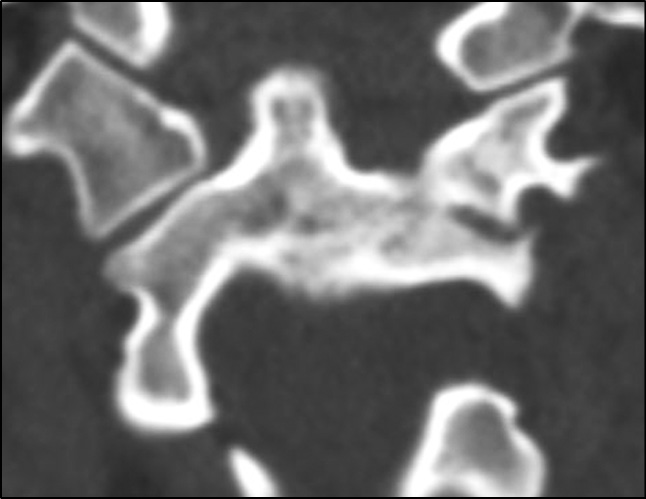

CT revealed gross violations of craniovertebral relationships: the Cruveilhier joint gap (atlantodental interval [ADI]) was 1.06 cm, and the space available for the spinal cord at the C1 level (SAC C1) was 5.17 mm. These changes indicate gross stenosis of the spinal canal. A bone block developed in the left lateral atlantoaxial joint (Fig. 3)

Fig. 3. Bone fusion in the region of the left lateral atlantoaxial joint.